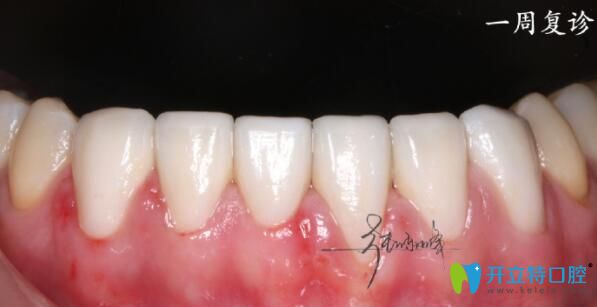

一周后復(fù)診拋光牙面,沒有任何問題,就當(dāng)做自己的牙齒這位男士說:“以后再也不擔(dān)心張口了”。

牙齒貼面后